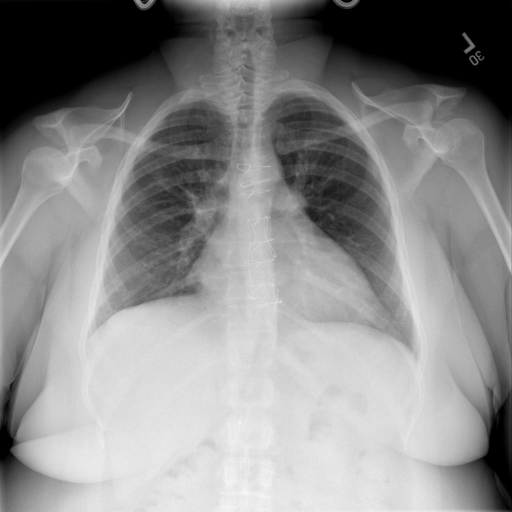

- (1)准备[诊疗报告(中文)](./data/Xray/openi-zh.json)和[X光影像](https://pan.baidu.com/s/13GBsDMKf6xBZBSHpoWH_EA?pwd=k9sh)在`data/Xray`文件夹下; - (2)开始训练: ```bash # 设置CUDA变量,主要是为了解决有时候直接训练而出现无法正确加载到显卡问题 export CUDA_VISIBLE_DEVICES=0,1,2,3 # 开始训练 bash finetune_XrayGLM.sh ``` 这里的复现过程非常简单,主要是很多过程我们都为大家准备好了,大家可以随时复现一个自己的`XrayGLM`。 ### 4.模型训练(通用) ## 效果展示 *以下效果来自于**低质量**的数据训练和权重 影像诊断: |X光影像|诊疗报告(医生)|XrayGLM| |:-|:-|:-| |![](./data/Xray/2_1.png)|根据X射线图像,心脏大小正常,肺部看起来很清晰。已经排除了肺炎、积液、水肿、气胸、腺病、结节或肿块的存在。该发现表明一切正常。换句话说,总体印象是胸部正常。|X光片显示,心脏大小正常。肺部没有气胸或胸腔积液的证据。骨骼结构看起来没有任何异常。总的来说,X光片表明没有发现急性心肺疾病的迹象。| |![](./data/Xray/2882_1.png)|X光图片显示没有扭曲的区域、可疑的骨质不透明度或胸腺积液。心脏大小轻微增大,但非常稳定。此外,没有气胸的证据,肺野也正常。总体来说,X光片显示没有急性心脏异常,但要注意轻微的心脏扩大。|X光片显示,心脏大小正常。肺部和纵隔轮廓清晰,没有气胸或胸腔积液的证据。骨骼结构完整,没有任何急性异常。| |![](./data/Xray/2577_1.png)|心影形态在正常范围内。没有急性骨质异常。有可能出现没有明显的吸水或肺实质状况的线索。没有大面积积液或气胸。有可能怀疑其有误吸或肺实质问题。为了确诊和治疗,可能需要进行适当的影像学随访。|心脏大小正常,肺部和纵隔轮廓清晰。没有急性异常或活动受限的证据。没有任何明显的气胸、胸腔积液或肺不张的迹象。此外,也没有发现任何局灶性骨质异常或其他急性疾病。| 多轮对话: |X光影像|诊疗报告(医生)| |:-|:-| |![](./data/Xray/861_1.png)|右侧主动脉突出观察到。心脏大小正常。胸部未发现明显的肺气肿、胸膜积液或可疑的肺部病变。报告指出已知右侧主动脉情况正常。| ```bash >> X光影像路径:./data/Xray/861_1.png >> 用户:这是一张什么图? >> XrayGLM:这张图片显示的是一张肺部检查的X光片。 >> 用户:请描述这张胸部X光片的诊断结果 >> XrayGLM:心脏大小正常,肺部清晰。没有急性心肺疾病的证据。 >> 用户:是否存在肺气肿? >> XrayGLM:没有肺气肿。心脏大小正常,肺部清晰。没有发现急性心肺疾病的证据。 >> 用户:平时饮食该注意什么? >> XrayGLM:饮食应该健康,均衡。建议增加蛋白质的摄入量,因为蛋白质有助于维持肌肉和骨骼的健康。多食用蔬菜、水果、全谷物以及健康的脂肪来源如橄榄油、鱼类等可以帮助获得足够的维生素和矿物质。此外,避免过度饮酒或吸烟,这些习惯可能会对心脏健康产生负面影响。 ``` ## 未来展望 1. 模型的能力更多来源于数据的支持,`OpenI-zh`作为微调数据集,其数据量足以支持研究,在更广泛的任务和性能表现上,我们认为**在大规模数据集上预训练并在高质量少量数据集上微调是一种可行的方案**; 2. 普遍意义的理解上,视觉多模态模型=视觉模型+语言模型。除了需要关注视觉模型信息与语言模型输出的搭配外,还需要**额外关注到语言模型的加强,在人机的对话中,尤其是医疗语言模型的问答上,除了专业的医疗问题回答,带有人文情怀的有温度的回答更应该是我们追寻的目标**。 3. **高精度的模型永远打不过大参数的模型**,如果在6B模型和13B模型上选择微调,请在资源充足情况下选择13B的大参数模型; ## 项目致谢 1. [VisualGLM-6B](https://github.com/THUDM/VisualGLM-6B)为我们提供了基础的代码参考和实现; 2. [MiniGPT-4](https://github.com/Vision-CAIR/MiniGPT-4)为我们这个项目提供了研发思路; 3. ChatGPT生成了高质量的中文版X光检查报告以支持XrayGLM训练; 4. [gpt_academic](https://github.com/binary-husky/gpt_academic)为文档翻译提供了多线程加速; 5. [MedCLIP](https://github.com/RyanWangZf/MedCLIP) 、[BLIP2](https://huggingface.co/docs/transformers/main/model_doc/blip-2) 、[XrayGPT](https://github.com/mbzuai-oryx/XrayGPT) 等工作也有重大的参考意义; ![](./assets/images/mpu.png) 这项工作由[澳门理工大学应用科学学院](https://www.mpu.edu.mo/esca/zh/index.php)硕士生[王荣胜](https://github.com/WangRongsheng) 、[段耀菲](https://github.com/IsBaSO4) 、[李俊蓉](https://github.com/lijunrong0815)完成,指导老师为檀韬副教授、[彭祥佑](http://www.patrickpang.net/)老师。 *特别鸣谢:[USTC-PhD Yongle Luo](https://github.com/kaixindelele) 提供了有3000美金的OpenAI账号,帮助我们完成大量的X光报告翻译工作 ## 免责声明 本项目相关资源仅供学术研究之用,严禁用于商业用途。使用涉及第三方代码的部分时,请严格遵循相应的开源协议。模型生成的内容受模型计算、随机性和量化精度损失等因素影响,本项目无法对其准确性作出保证。即使本项目模型输出符合医学事实,也不能被用作实际医学诊断的依据。对于模型输出的任何内容,本项目不承担任何法律责任,亦不对因使用相关资源和输出结果而可能产生的任何损失承担责任。 ## 项目引用 如果你使用了本项目的模型,数据或者代码,请声明引用: ```bash @misc{wang2023XrayGLM, title={XrayGLM: The first Chinese Medical Multimodal Model that Chest Radiographs Summarization}, author={Rongsheng Wang, Yaofei Duan, Junrong Li, Patrick Pang and Tao Tan}, year={2023}, publisher = {GitHub}, journal = {GitHub repository}, howpublished = {\url{https://github.com/WangRongsheng/XrayGLM}}, } ``` ## 使用许可 此存储库遵循[CC BY-NC-SA](https://creativecommons.org/licenses/by-nc-sa/4.0/) ,请参阅许可条款。